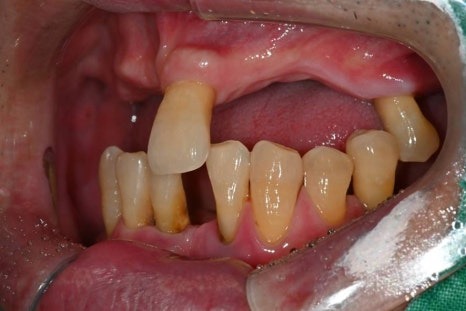

· 상악은 잇몸뼈가 매우 얇고 치아가 거의 남아 있지 않은 상태

· 하악은 부분 결손과 앞니의 심한 동요

· 식사가 어려울 정도로 기능 저하가 심한 상태

치료 전

치료 후